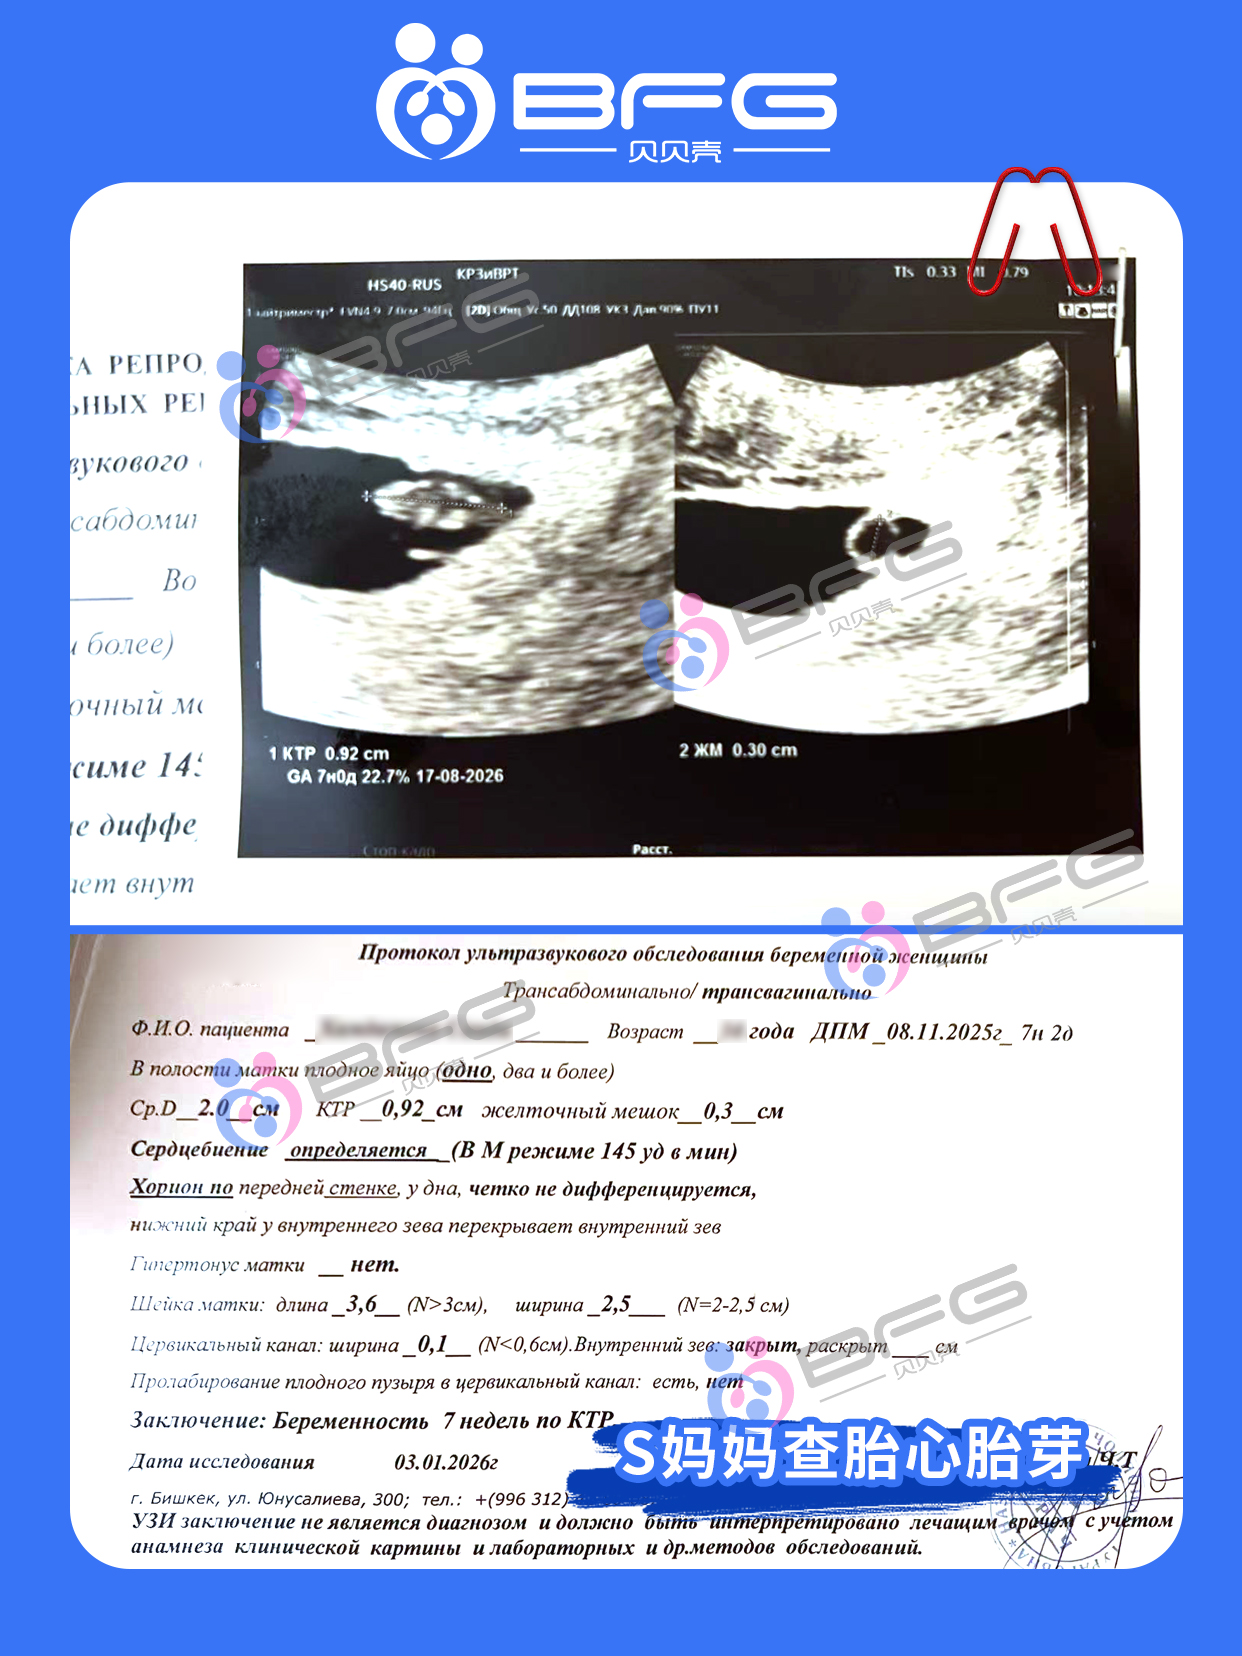

2位❤️妈妈孕7周超声见胎心胎芽,小生命们的心跳砰砰砰有力!愿产检一路绿灯,宝宝们健康成长👏👏👏